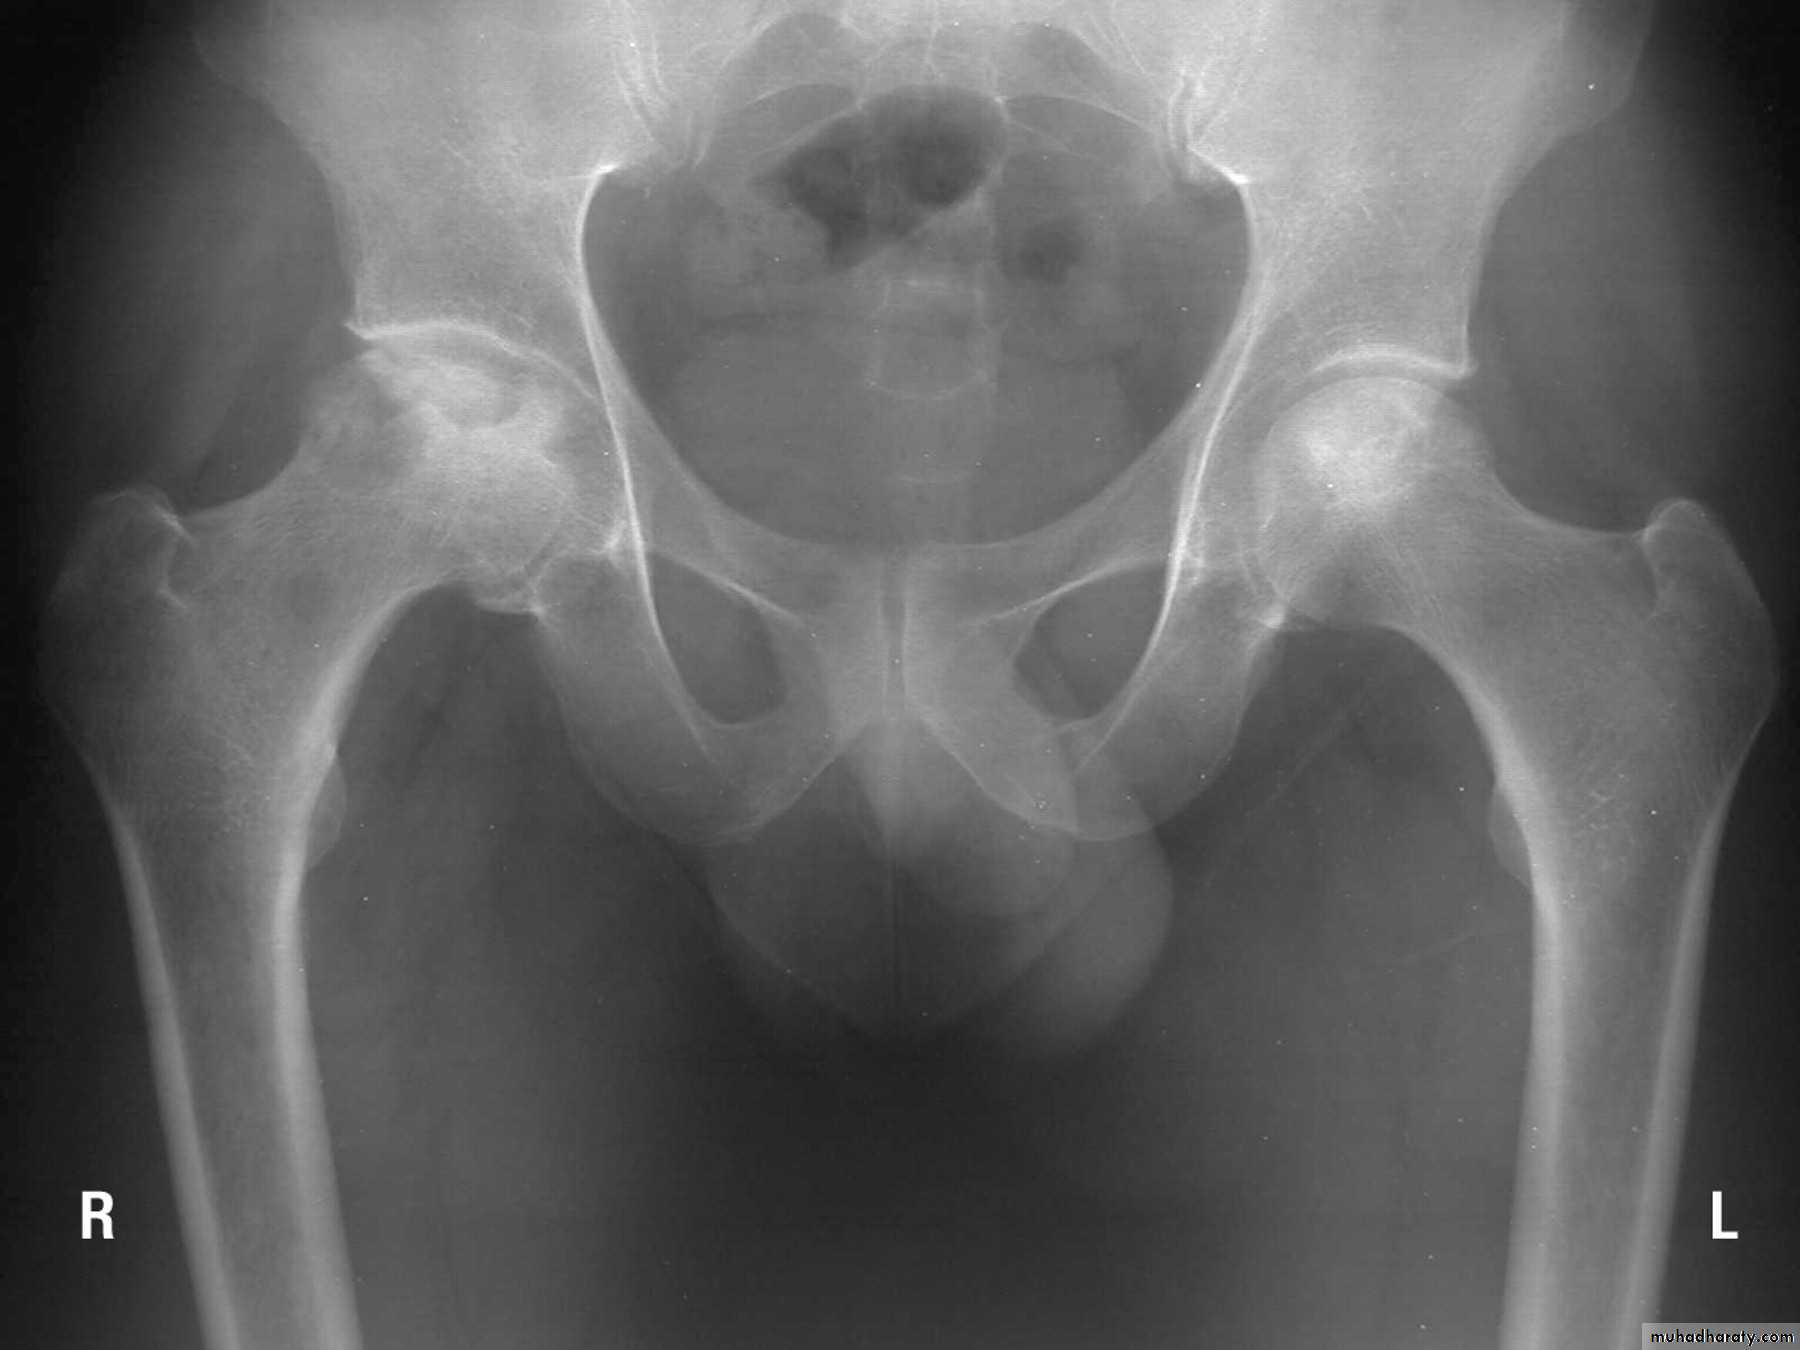

Avascular necrosis :

Certain regions are problematic for their tendency to develop ischemia and bone necrosis after injury.They are:

- the head of the femur (after fracture of the femoral neck or dislocation of the hip);

Accurately speaking, this is an early complication of bone injury, because ischemia occurs during the first few hours following fracture or dislocation.

However, the clinical and radiological effects are not seen until weeks or even months later.

Clinical features of AVN :

Painincreased bone density in the radiography

Treatment :

Femoral head AVN – total hip arthroplasty or arthrodesis